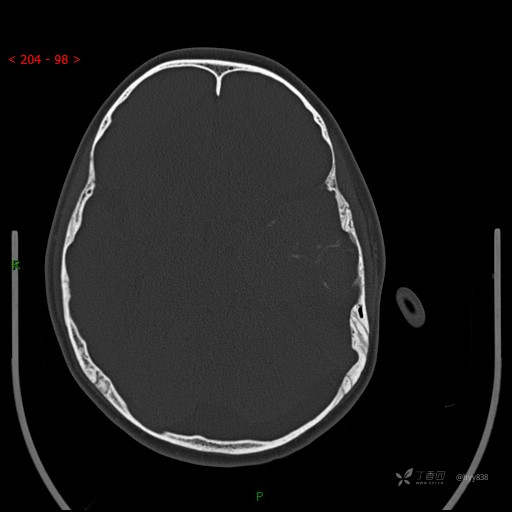

“典藏”病例分享。10岁儿童,头痛头晕一周余,CT、MRI 都有---结果公布~

简要病史:患者于一周前无明显诱因开始出现头痛头晕,无恶心呕吐,无肢体抽搐,无寒颤高热,无腹胀腹泻,无视力下降及视野缺损,上述症状休息后可稍缓解,未引起重视。 2天前患者头痛头晕不适加重,伴有恶心感,无呕吐,遂到当地人民医院行头颅CT检查示:左侧颞部占位性病变,今日家属为求进一步治疗,来我院门诊求治。门诊拟“左侧颞部占位性病变”收入我科。 患病以来,患者精神、饮食、睡眠尚欠佳,大小便如常,体力体重无明显变化。

临床诊断:左侧颞部占位

颅脑CT扫描